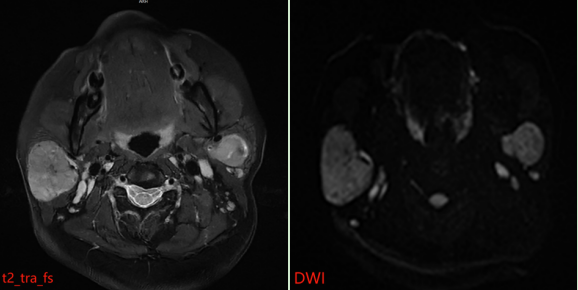

患者接受了磁共振(MR)检查,影像表现如下:

MR 表现:双侧腮腺浅叶下极见结节状略混杂信号,T1 以低信号为主、T2 以 稍高信号为主,DWI 呈稍高信号,ADC 图呈稍低信号,边界清晰,增强扫描病变中等强化,强化较均匀,其内见点状无强化影。